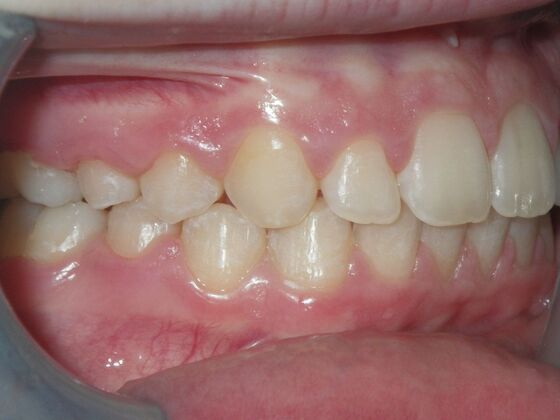

Orthodontics: Case 2

Patient is 9 years old and presents with 100% overbite and blocked out upper and lower lateral incisors. Both upper central incisors are palatally inclined causing a lack of space available for most anterior teeth. Advised her parents that she needs Phase I Interceptive Orthodontic treatment to provide room for all upper and lower front teeth. Phase I treatment was begun and finished, then began Phase II treatment shortly thereafter to finalize case. Removable retainer were fabricated for retention.